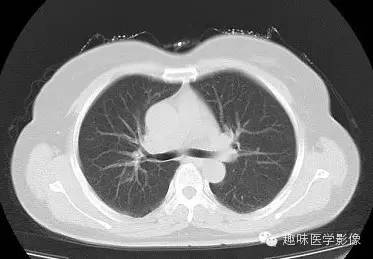

两肺未见明显异常。纵隔左侧见血管影,经主动脉弓与左肺肺门之前向下走行,汇入冠状静脉窦。

永存左上腔静脉